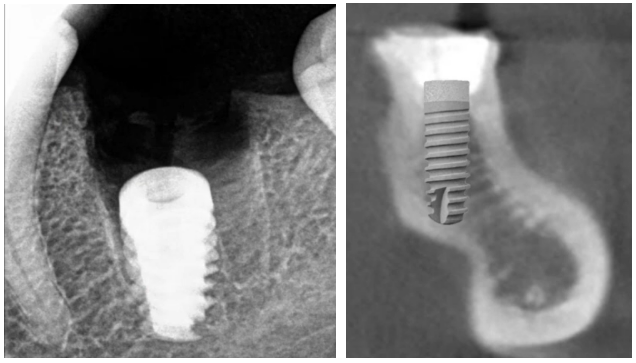

Errors in vertical implant positioning: on the left, the implant is too deep, significantly below the crestal bone level, which is why the socket of the extracted tooth did not heal completely; on the right, the implant is too long, almost passing through the jaw. YouTube/ Dr. Sergey Rozhnov /sergiodontolog

If it’s the upper jaw, the implant’s apex may penetrate the maxillary sinus. If it’s 2-3 mm, sinus lifting is generally not necessary. The main thing is that the bone thickness is sufficient to secure the implant. Standards and indications for sinus lift are a separate topic, so we won’t discuss it in detail.The lower jaw is at risk of damaging the mandibular nerve or artery.In any case, you should not make mistakes like those in the illustrations below.